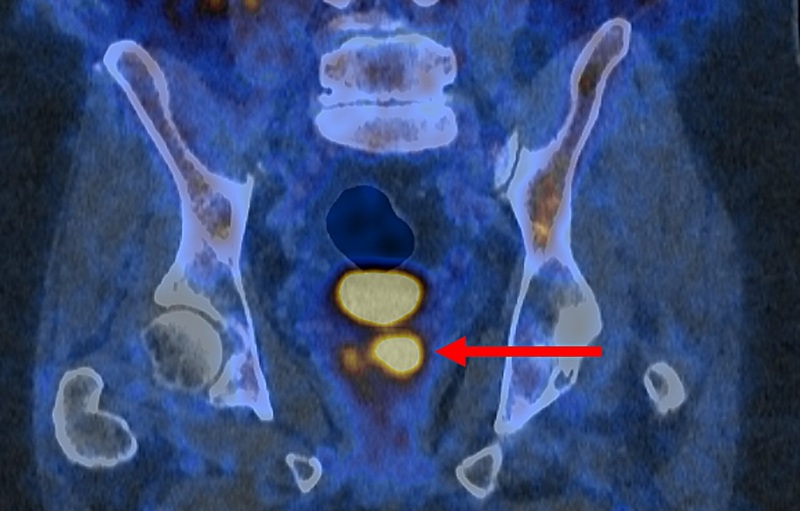

- New Imaging Solution Improves Survival for Patients with Recurring Prostate Cancer